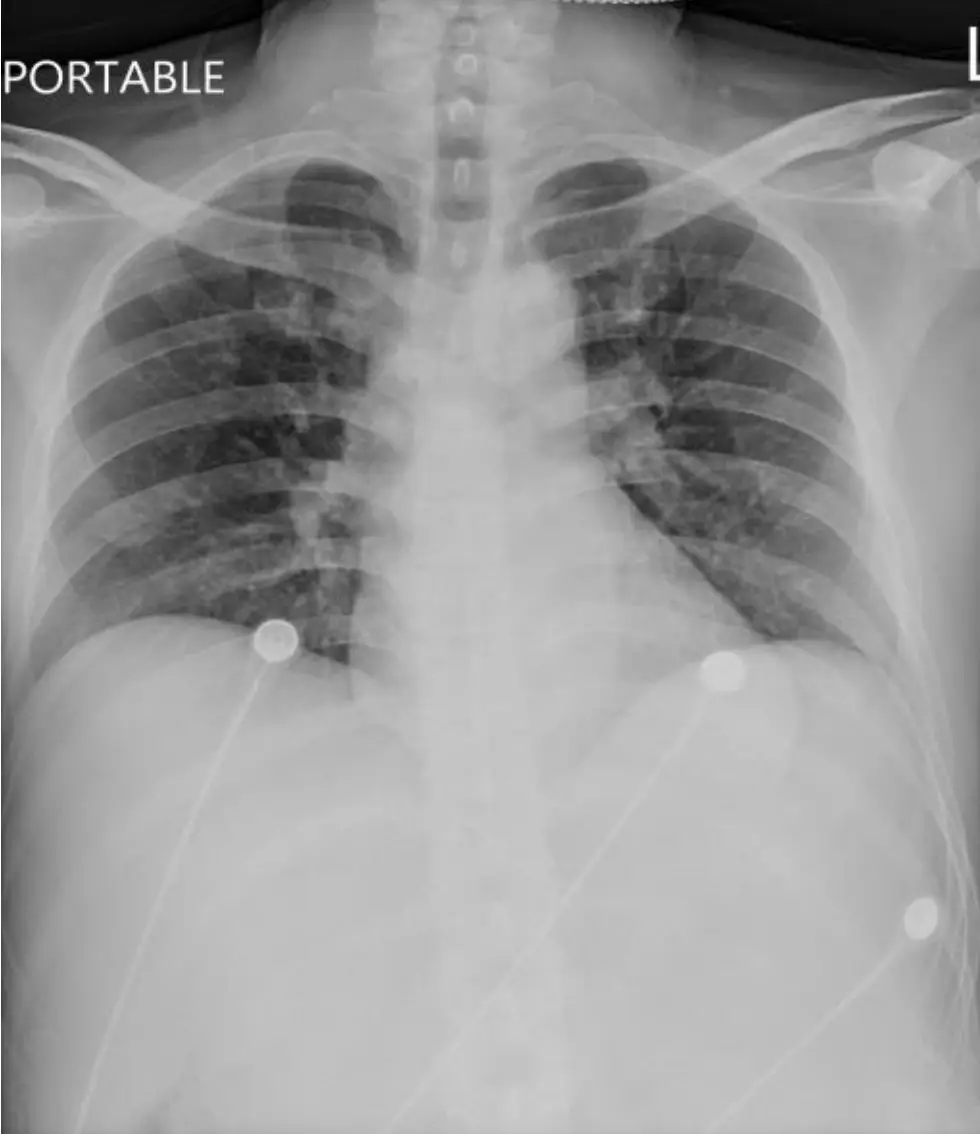

胸部X光:

- 心臟大小正常(mild‐normal),肺野未見明顯充血、肺紋理增粗或浸潤影,無急性肺炎或肺水腫所見。

- 鎖骨下無異常置入物,血管影及縱隔結構均屬正常,無心源性肺水腫或心臟衰竭徵象。

綜合影像,患者為「穩定型」(hemodynamically stable)但症狀(心悸、頭暈、呼吸